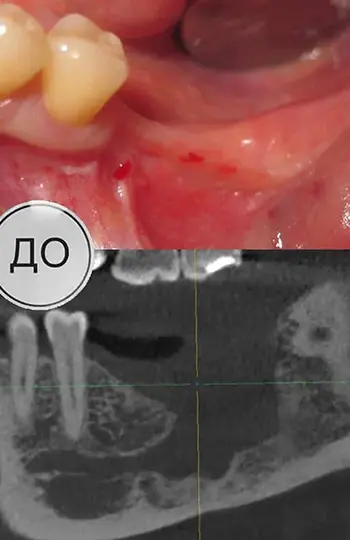

Імплантація

Збільшення обсягу кістки.

Після видалення кісти (не в нашій клініці) відсутні жувальні зуби, наскрізний дефект щелепи, в цій зоні нижньощелепний нерв проходить поза кістковими структурами. Пластика кістки та м’яких тканин, імплантація.

Хірург Святослав Вантурінов.

Цільноцирконієві коронки на гвинтовій фіксації.